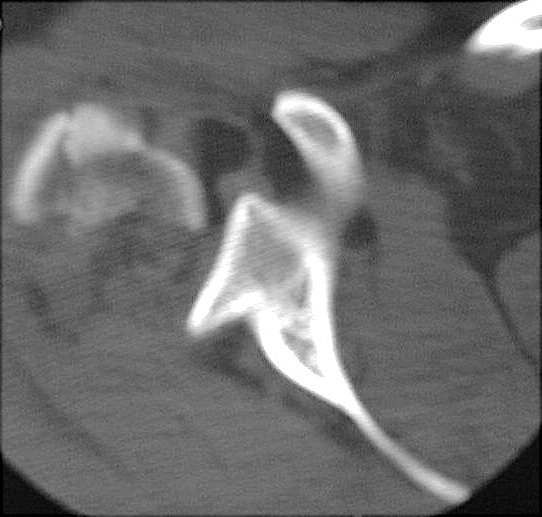

Images 2 and 3: CT examination at the level of the glenoid and presented in soft tissue and bone window technique. The lipohemarthrosis of the glenohumeral joint is identified as a globular focus of fat layering upon a small amount of blood. CLICK TO ENLARGE.